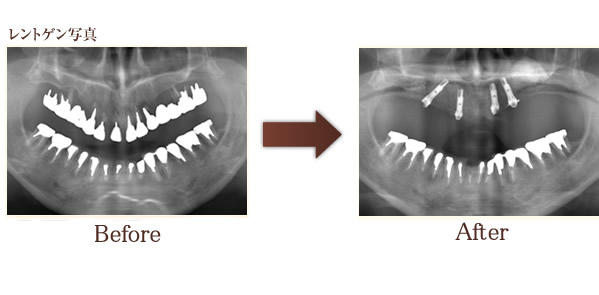

レントゲン写真を撮影し、治療計画を立てます。

All-on-4の治療症例